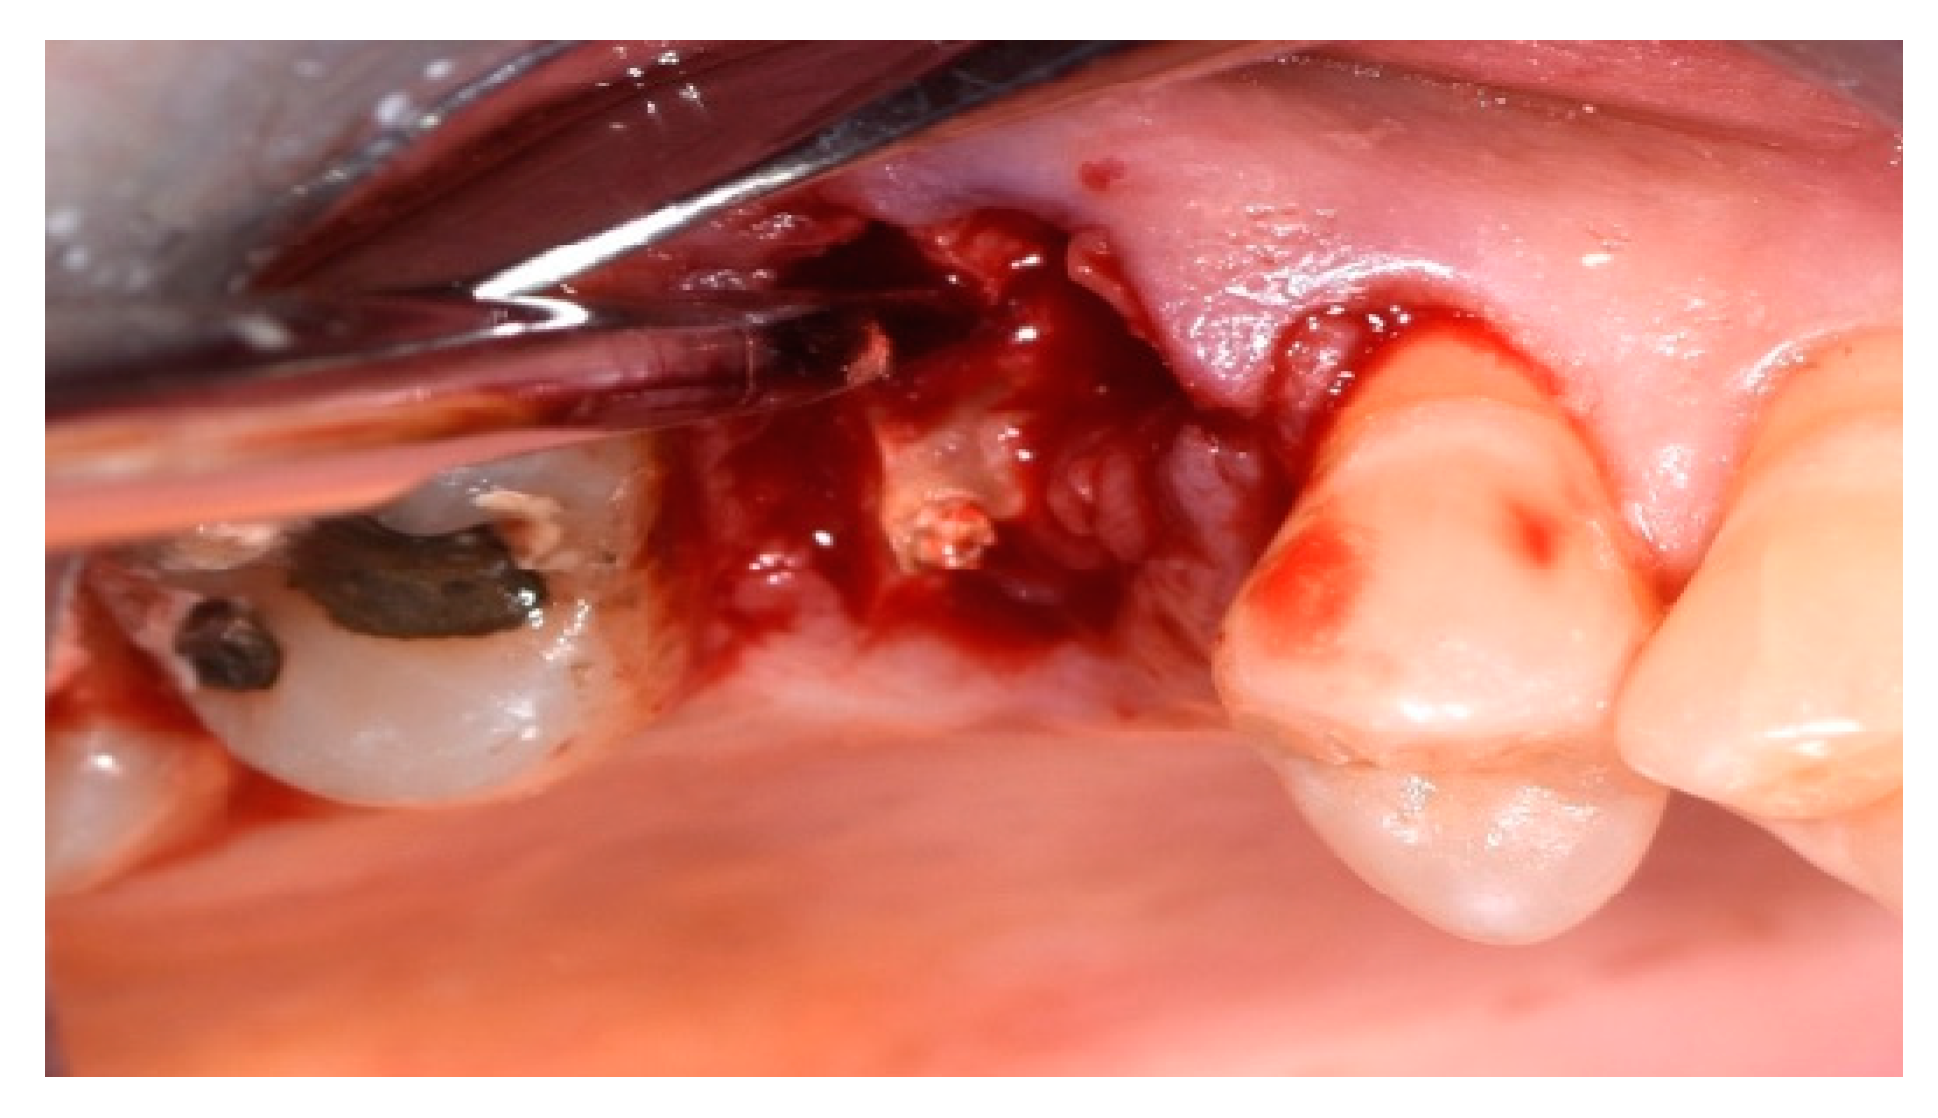

2.4. Surgical Procedure, Evaluation at Follow-Up, and Collection of Radiographic Data